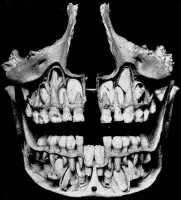

Есть зубы - есть проблемы. Нет зубов - нет проблем.

Видишь зубы ? Нет. А они есть